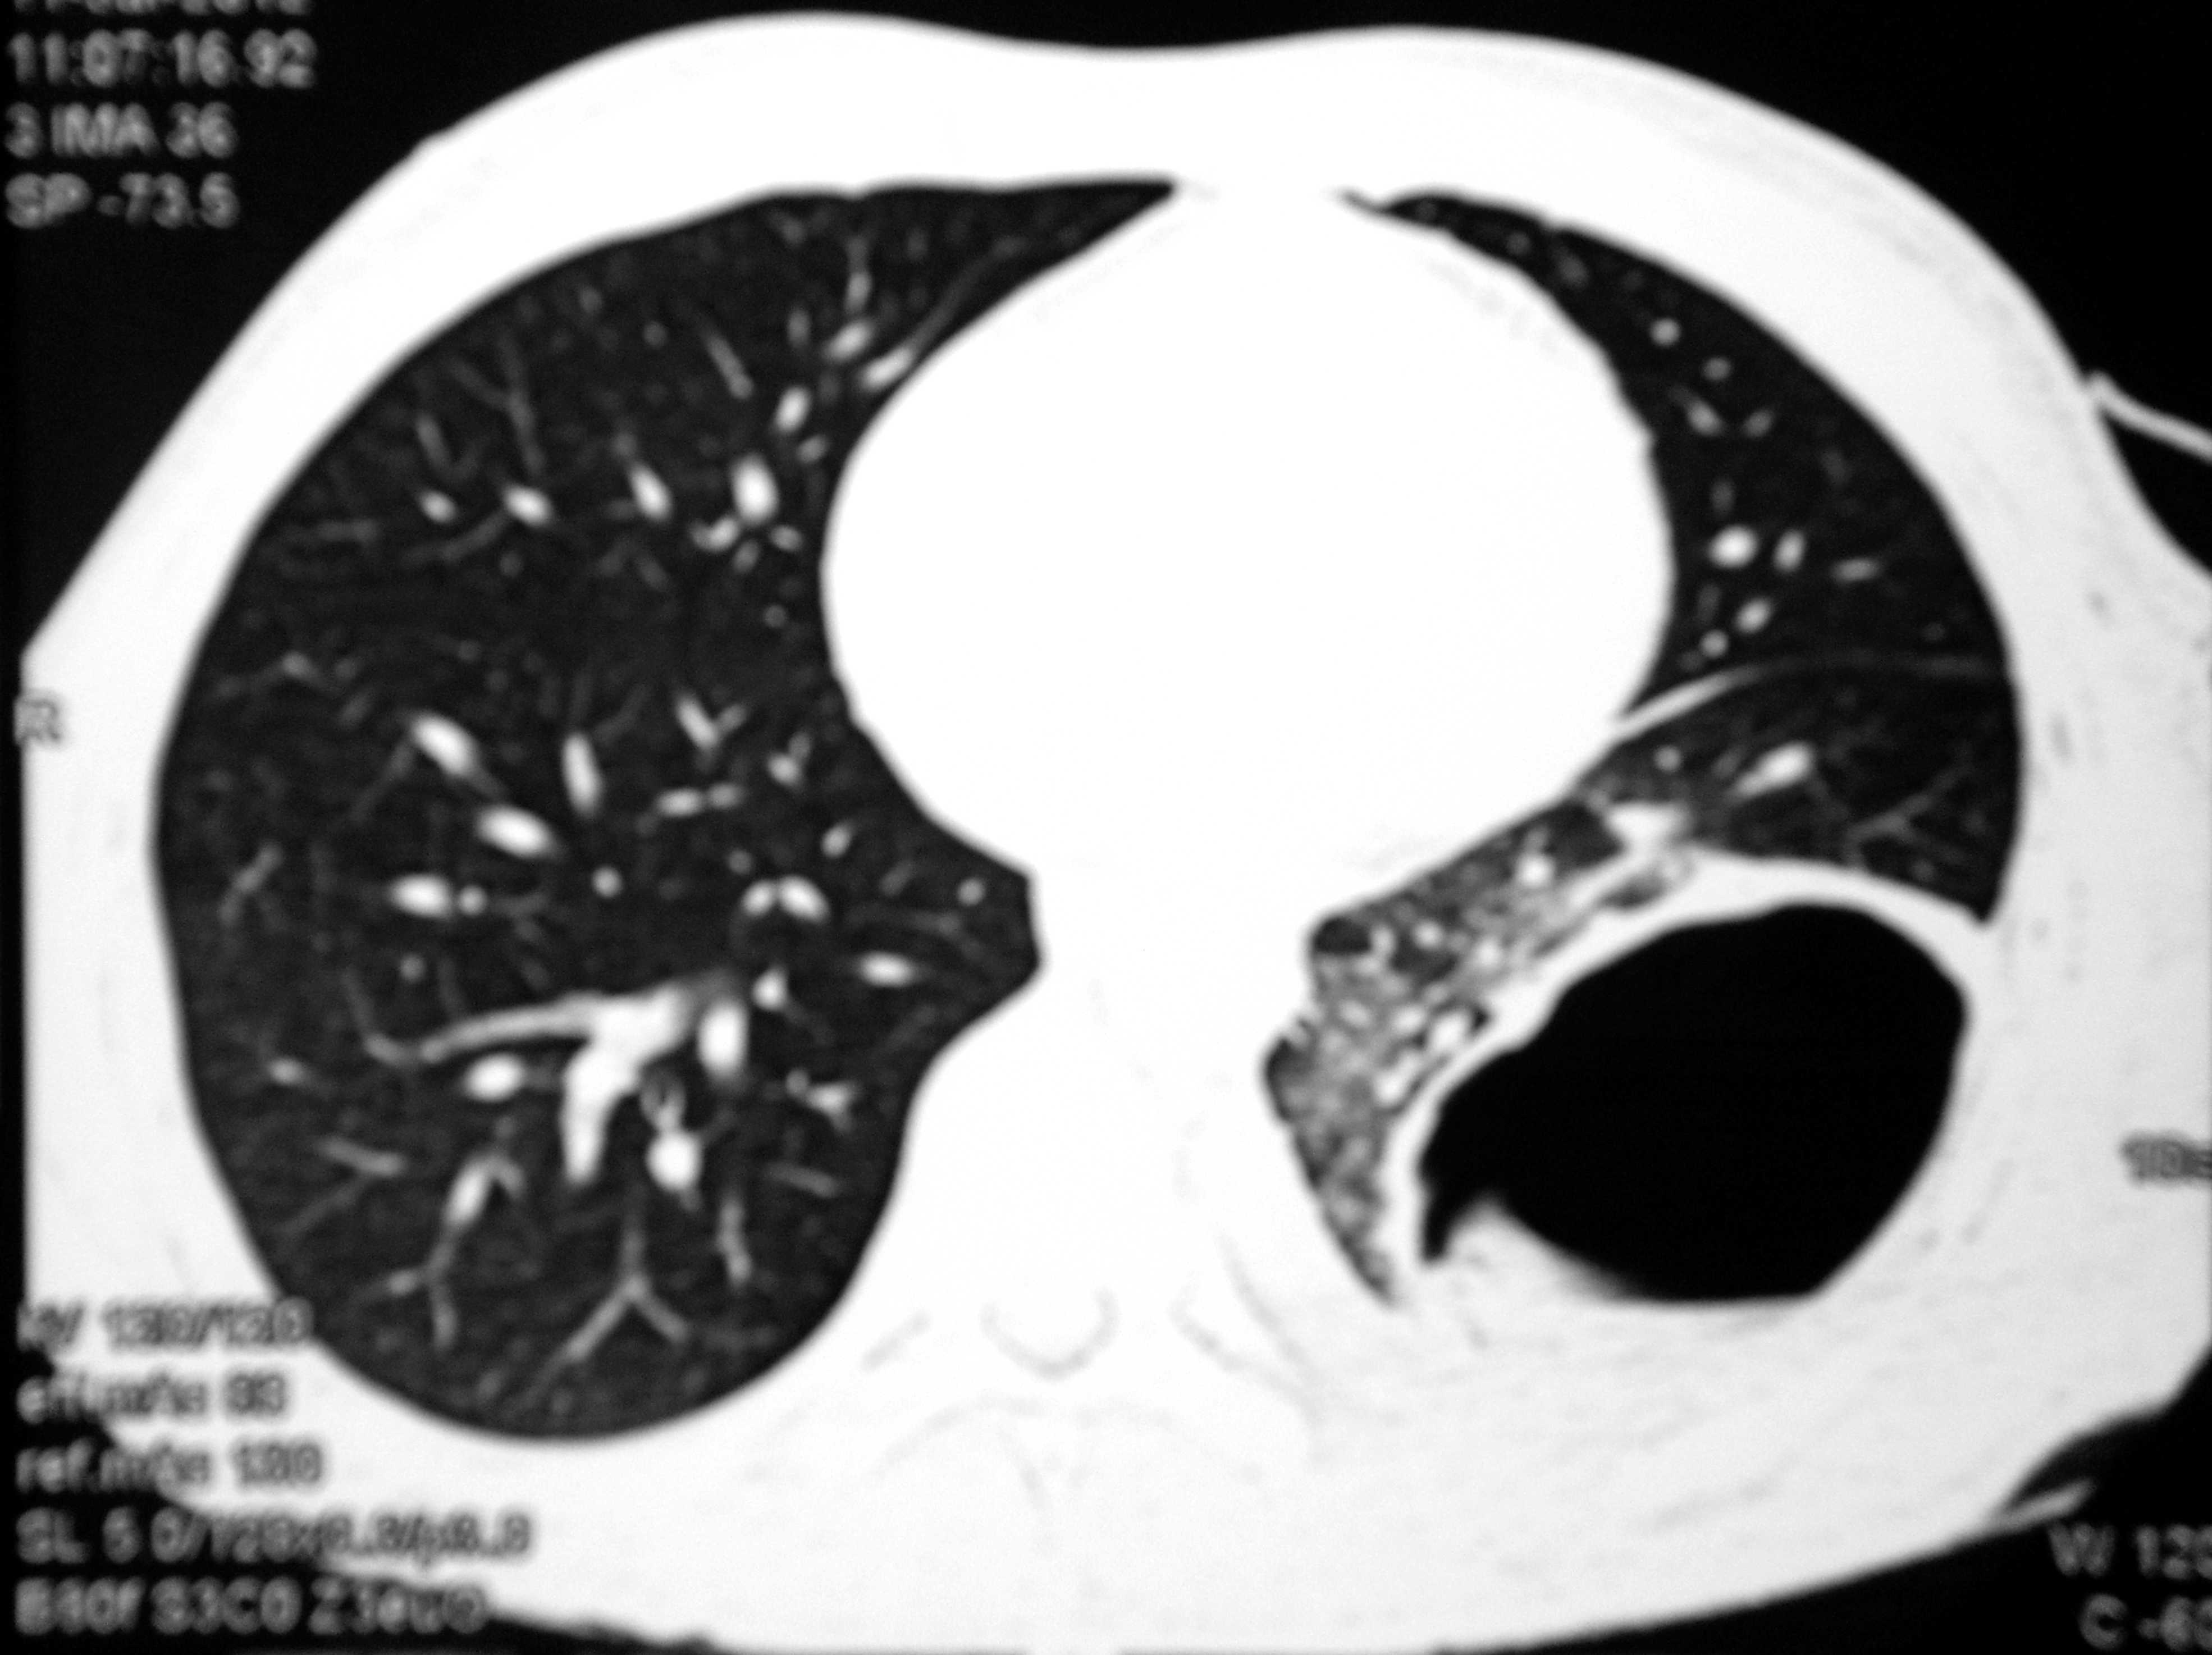

On admission, oral temperature was 100°F, pulse rate was 100/minute, Blood Pressure was 120/80 mmHg, Respiratory rate was 30/min. There was decreased air entry on left lung auscultation and one Intercostal drain (ICD) in situ on left side. Per abdomen examination was insignificant except hepatomegaly. Chest X-ray PA view after aspiration showed hydropneumothorax with clear-cut cyst margins on the left lower region with ICD inside (Figure 1). CECT abdomen and chest revealed two hydatid cysts in the right lobe of the liver (Figures 2 & 3). After all preoperative evaluation, patient was found fit for the surgery. His all hematologic and biochemical parameters were within normal limits. Therefore, it was planned to deal with the lung and liver hydatids at the same sitting under general anesthesia first with liver followed by lung hydatid cyst.

Figure 3 CECT Chest revealed ruptured hydatid cyst in left lower lobe.